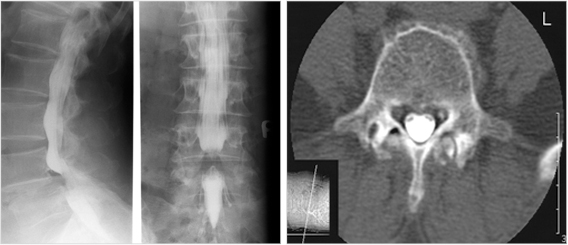

조영술 검사

조영술 검사는 척추 진단 검사로써 x-ray선에 민감한 특수 조영제를 주입하여 x-ray선 촬영시 척추, 척수 및 신경근육의 부분이 더 또렷하게 보여지게 하는 역할을 하여 병변의 문제점을 보다 확실하게 검사할 수 있습니다.

척추 조영술 및 전산화 단층촬영

추간판 조영술